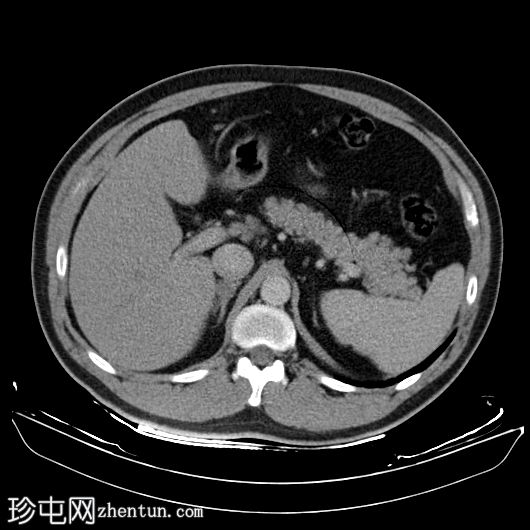

随访(16 个月后)

CT

轴位

平扫

2.jpg

轴位增强扫描

动脉期

3.jpg

右下肺支气管内肿块较前增大,现已延伸至中间支气管,并可见对比剂强化。右下肺阻塞性肺不张。

左下肺支气管出现新的类似肿块。